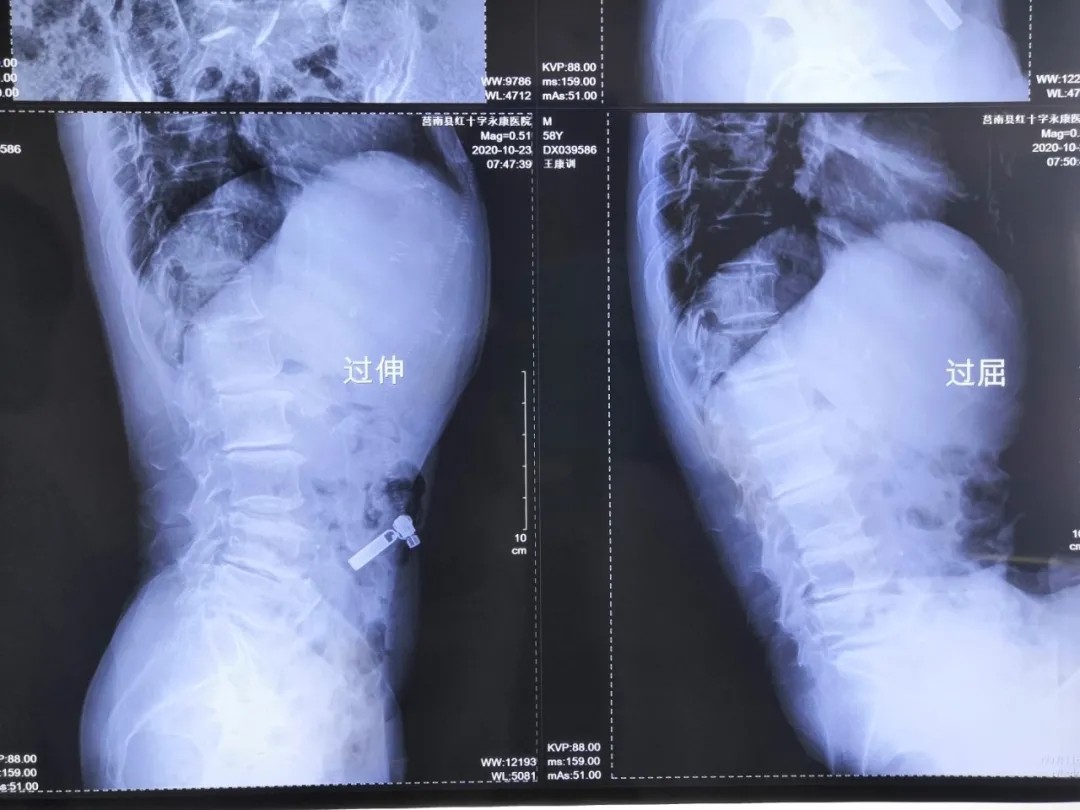

影像资料:

腰椎管狭窄症;腰椎间盘突出症;老年退变性侧弯。